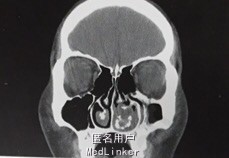

体检时鼻腔异常堵塞,鼻甲肥厚。CT示左侧鼻腔出现全腔异常密度影,累积全层鼻甲,密度稍高,未侵犯右侧鼻腔。